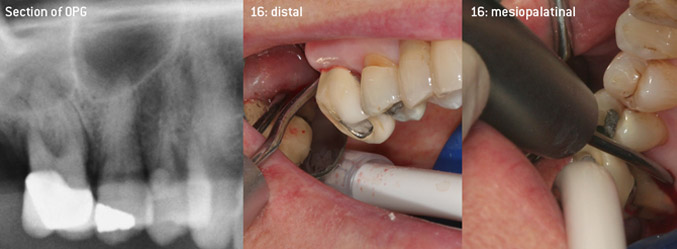

In order to permit this in complicated cases with advanced attachment loss and with involvement of furcation, W&H now offers the new 3AP working tip (Figure 1) for air scalers, the ideal instrument for removing hard and soft deposits on the root surface not only atraumatically but also rapidly and efficiently.

As initiators of the development of the new diamond-coated 3AP air scaler tip, the two dentists recognized the need for improvement of the handling restrictions of the commercially available diamond-coated tips, especially during furcation treatment and when working in tight intraosseous pockets. This should be possible for both non-surgical (Figure 2) and surgical (Figure 3) procedures.

The aim was to develop a universally applicable tip in order to avoid time-consuming tip changes. In addition, it should be easier to use the new working tips in tight intraosseous pockets from distal and at the distal furcation entrance of maxillary molars, allowing more effective use of instruments as a result. This was achieved by employing an instrument curve with a larger diameter (Figure 1), which is highly advantageous for closed debridement on teeth with advanced attachment loss and involvement of furcation in particular (Figure 4).